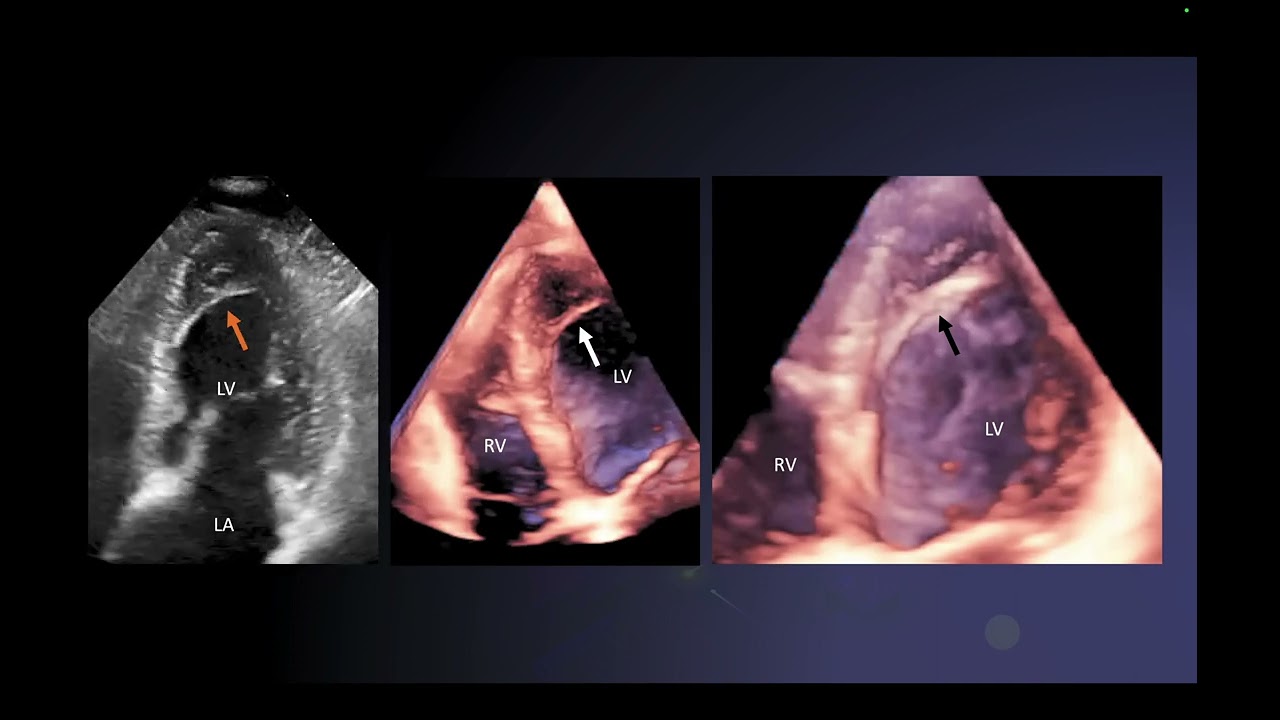

Four Chamber View is Not Normal

This video describes subtle signs on fetal echo which can work as a lead to investigate further.